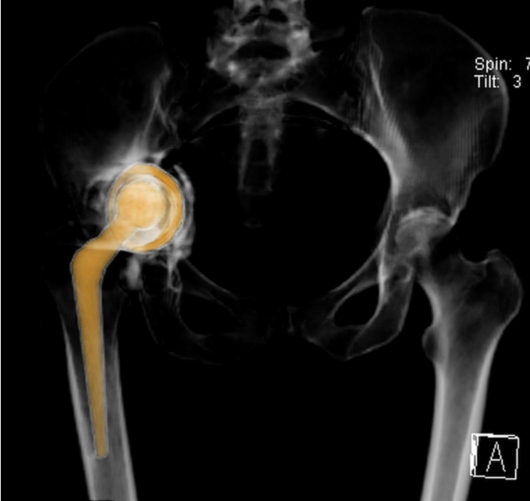

Practico una ortopedia centrada en usted como paciente, moderna, mínimamente invasiva y basada en evidencia científica. Me mantengo en constante actualización nacional e internacional y estoy certificado en cirugía de reemplazo articular con asistencia robótica con el sistema Mako® de Stryker, una tecnología de última generación para el reemplazo de cadera y rodilla, la más avanzada de Latinoamérica y el mundo.

Gracias a la planificación quirúrgica en modelos tridimensionales personalizados, este sistema permite una precisión milimétrica, lo que se traduce en:

Mayor estabilidad de la prótesis